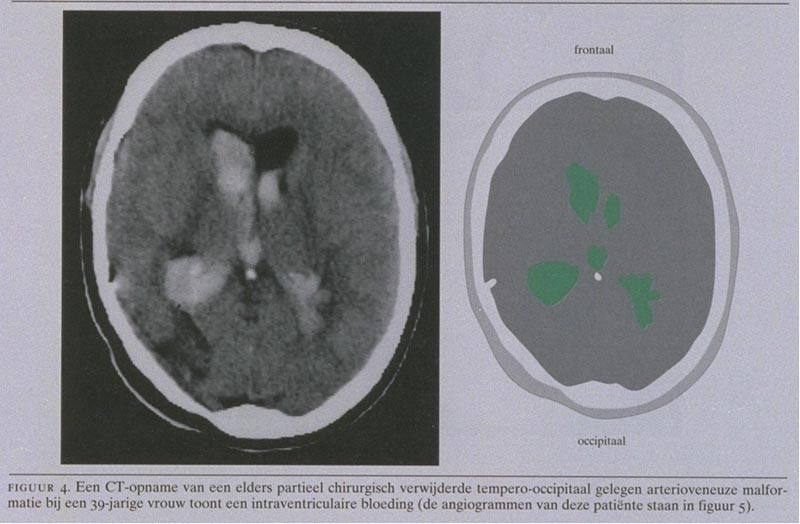

In een periode van 35 maanden werden door de werkgroep Neurovasculaire Interventie Tilburg 115 patiënten met een AVM gezien. De gemiddelde leeftijd was 41,8 jaar (uitersten: 6-72). De voornaamste klinische manifestatie was bij 65 patiënten (56,5) een bloeding, bij 31 patiënten (27,0) epilepsie, bij 7 patiënten (6,1) neurologisch uitval en bij 2 patiënten (1,7) hydrocefalus; bij 10 patiënten (8,7) werd de AVM bij toeval gevonden. De behandeling bestond uit operatie, stereotactische bestraling met het ‘gamma-knife’ en embolisatie. Embolisatie vond voornamelijk plaats teneinde de AVM te verkleinen om operatie of bestraling mogelijk te maken.

Van de 115 patiënten waren er 5 naar de werkgroep verwezen voor alleen een behandeladvies; bij hen vond eventuele behandeling elders plaats. Van de resterende 110 patiënten werden 84 wel behandeld (76,4) en 26 (23,6) werden om uiteenlopende redenen niet behandeld. Van de 84 behandelde patiënten werden 17 (20,2) alleen geopereerd, 17 (20,2) werden alleen bestraald en 12 (14,3) ondergingen alleen embolisatie. Operatie na embolisatie vond plaats bij 8 patiënten (9,5) en bestraling na embolisatie bij 26 (31,0). Bij 4 patiënten vond om uiteenlopende redenen een ongebruikelijke combinatie van deze behandelingen plaats.

Voorlopig was bij 35 van de 84 behandelde patiënten (41,7) de AVM geheel verwijderd of geoblitereerd; 39 patiënten wachtten nog op het definitieve resultaat van bestraling. Bij 5 patiënten werd opzettelijk een partiële embolisatie uitgevoerd. Bij 5 patiënten (6,0) werd het vooraf gestelde doel niet bereikt met embolisatie. De morbiditeit bedroeg 4,8 (4 patiënten) en de sterfte 1,2 (1 patiënt).